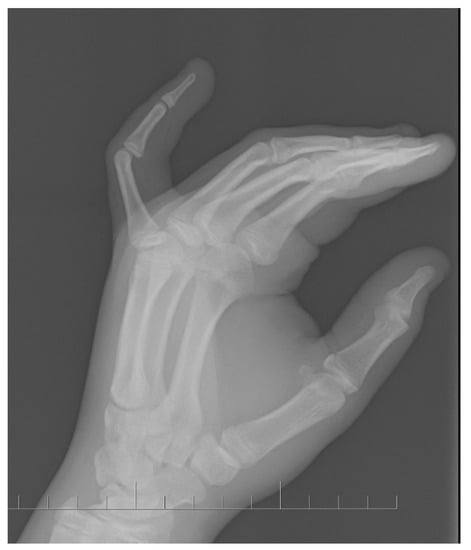

5. Case Report